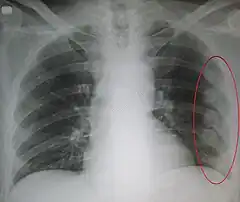

![]() Radiografía de tórax en la que son visibles varias fracturas costales señaladas por un óvalo en el hemitórax izquierdo. | ||

El diagnóstico se basa en la sintomatología y la exploración del paciente que detecta una serie de signos específicos. Las pruebas complementarias más utilizadas para confirmar el diagnóstico son la radiografía de tórax y la tomografía axial computarizada en caso de traumatismos graves.[2]